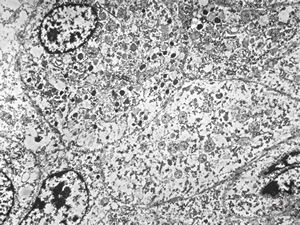

F, 44y. | carcinoid